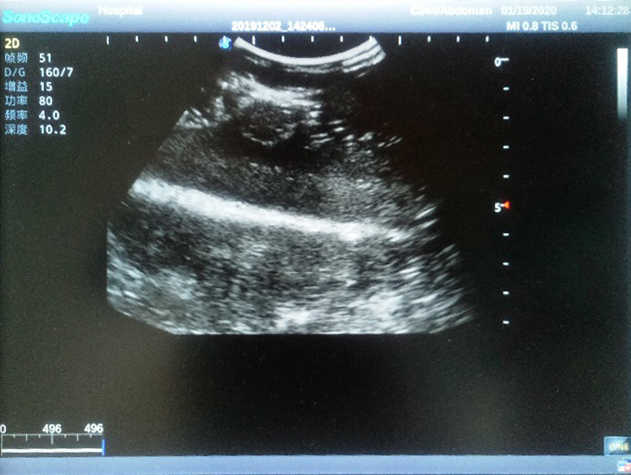

Breast Ultrasound Examination Model

Model TYE1568

Outline

The Breast Ultrasound Examination Model allows users to develop and practice the skills necessary to gain proficiency in breast palpation, using ultrasound for normal and abnormal imaging and biopsy. It simulates adult female breasts with realistic size and appearance.

Skills Gained

· Breast palpation

· Breast ultrasound examination

· Using ultrasound to target the lesions for biopsy

Features

· Realism:

1)  True-to-life size and appearance necessary to provide realistic practice for trainees

2)  Soft and elastic skin; realistic feel and touch

· Key Features:

1)  Made up of two breast models and a pedestal, easy to install and remove

2)  Each model contains 8 space-occupying lesions of varying sizes, different in touch, elasticity and ultrasonogram

3) Space-occupying lesions present in both the four breast quadrants and the Tail of Spence

4) Biomimetic material allowing users to see clear and real normal tissues and space-occupying lesions that are hyperechoic, hypoechoic and isoechoic as they would see in the clinical environment